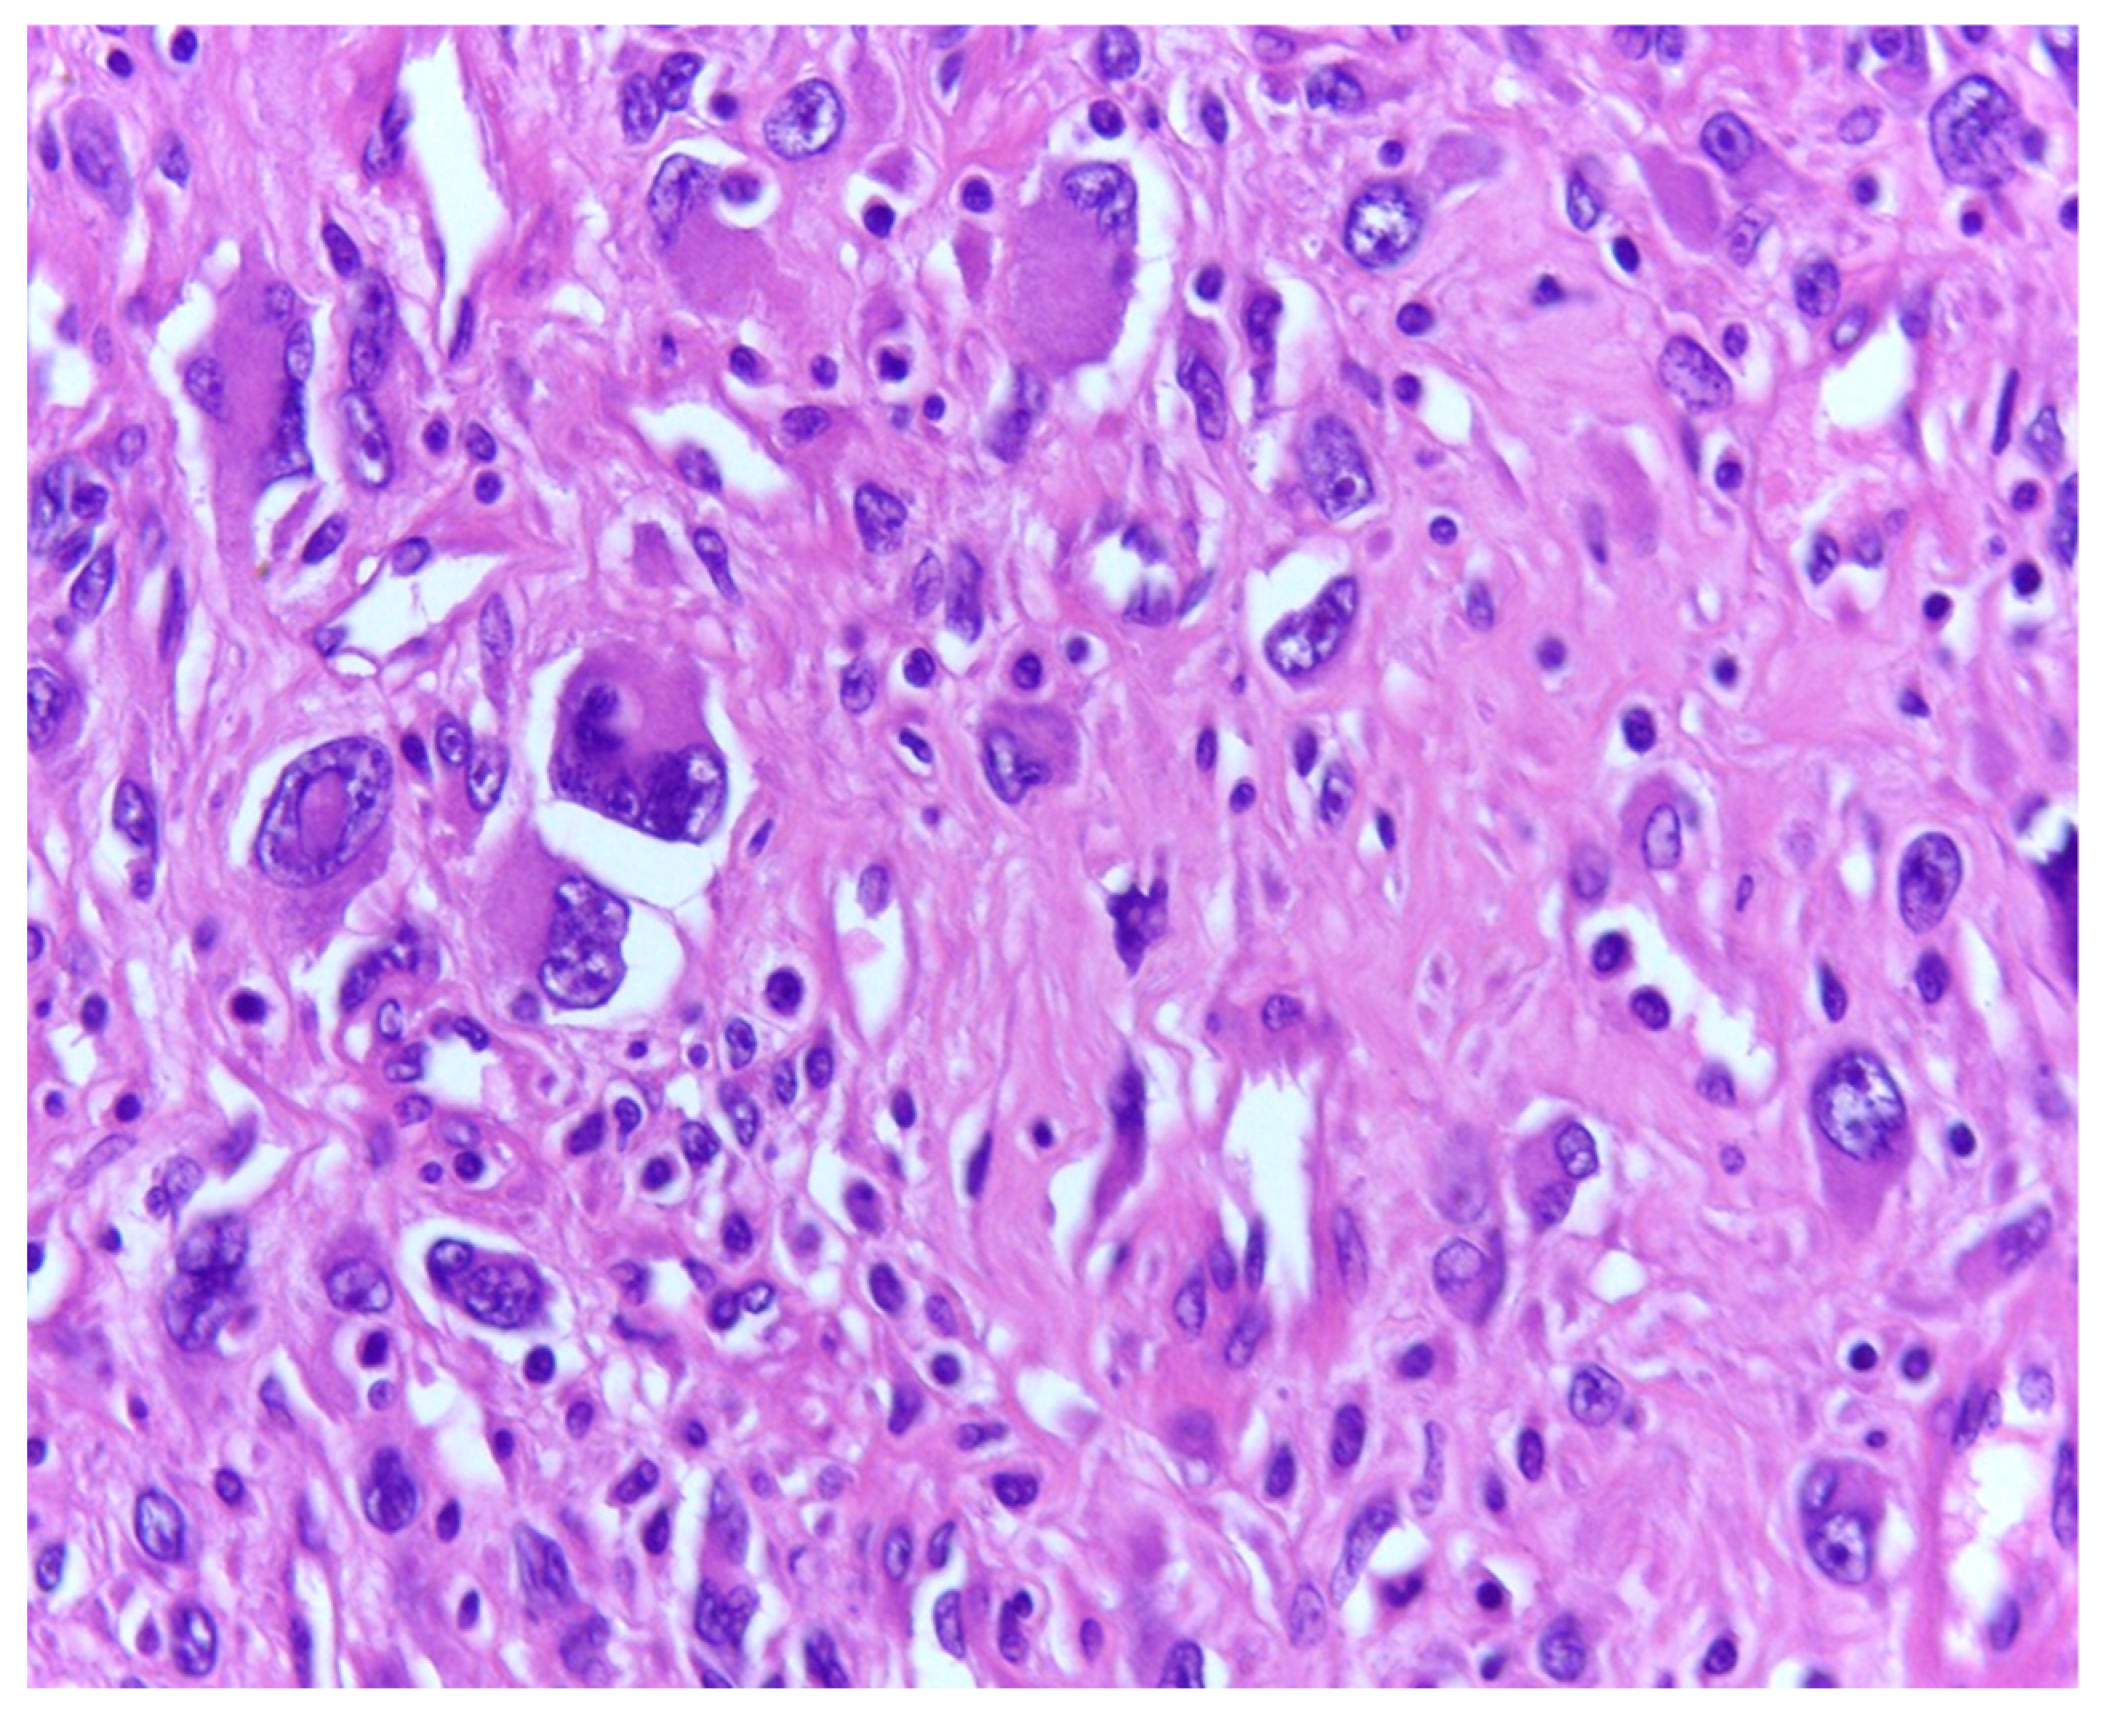

3.1. Tumor Grade

- Ciongariu, A.M.; Țăpoi, D.A.; Dumitru, A.V.; Bejenariu, A.; Marin, A.; Costache, M. Pleomorphic Liposarcoma Unraveled: Investigating Histopathological and Immunohistochemical Markers for Tailored Diagnosis and Therapeutic Innovations. Medicina 2024, 60, 950. [Google Scholar] [CrossRef] [PubMed] [PubMed Central]